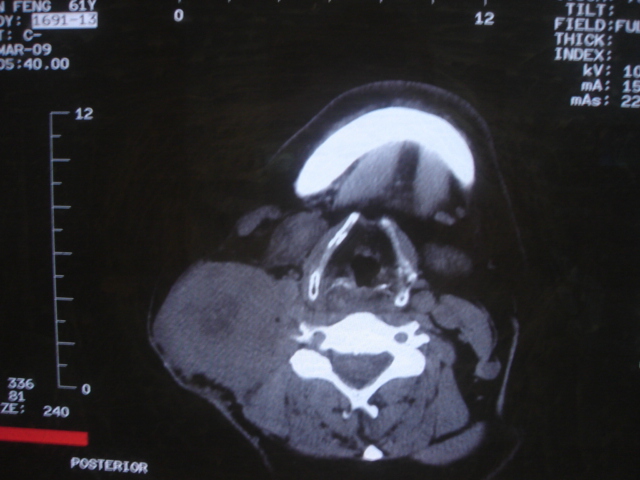

标题: CT18584:甲状腺Ca 喉转移?

患者 男 61  甲状腺ca术后7年 颈部淋巴结转移

声门下区表面不光整,增厚呈局限性突起,未见局部浸润.

考虑----颈部淋巴结转移,不排除---喉乳头状瘤可能.

右侧颈部淋巴结转移,右声带乳头突起,乳头状瘤可能性大。

1)右侧颈部淋巴结转移瘤。2)右侧声带新生物,性质待定;建议喉镜检查(活检)。